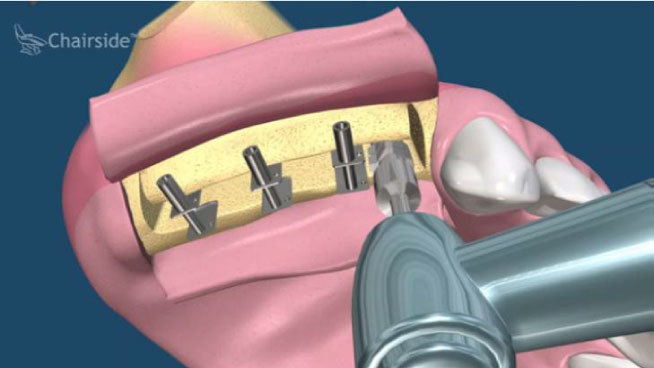

當我們遇到骨脊萎縮嚴重的區域(前、後牙區皆可能)時,可能會使用劈骨術(split technique)來增加骨脊的寬度,以便順利的植牙。而傳統劈骨術的做法技術需求性比較高,可以增加的骨脊寬度有限,而且如果骨脊因劈斷而有游離的情形時,那將損失更多得骨質。改良式的骨脊劈開術,可以得到較多與較可預測性的骨植增生,而且操作較為簡單(圖17-21)